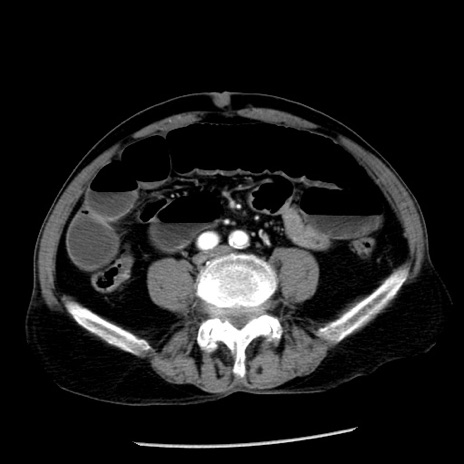

症例26(横断像)

【症例】80歳代男性

【主訴】嘔吐

【現病歴】昨晩2回嘔吐あり、今朝になっても嘔吐あり。来院。

【既往歴】胃潰瘍

【身体所見】意識清明、BT 37.6℃、BP 166/95mmHg、HR 100bpm、SpO2 97%、腹部:平坦・軟、腸蠕動音聴取良好、圧痛なし。

【データ】WBC 21900、CRP 1.46